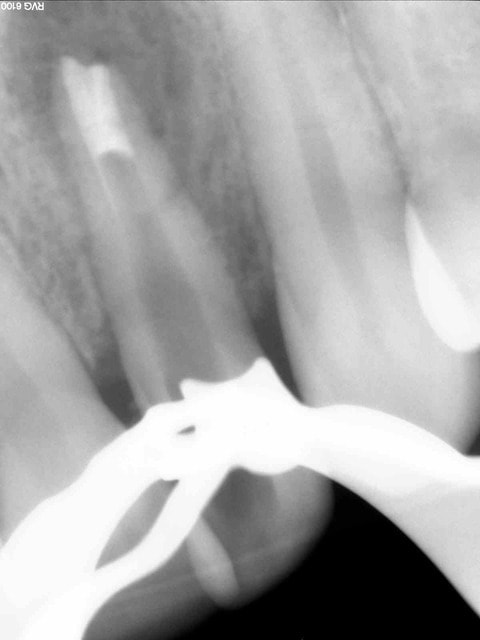

photos jointes: cas de resorption externe avec à l'origine faux canal, félure ou juste la resorption qui avait atteint le canal...

Obturée à la biodentine allongée, pose de srew post titane dans la foulée de l'obturation, un moignon compo a été réalisé ensuite.

Dent traitée en urgence (abcès), ça saignait mais j'ai pu cauteriser (merci lokki), une galère si j'avais voulu mettre de la gutta.... perdue pour perdue j'ai tenté le truc, c'était en janvier 2014 et la dent, recoiffée depuis est toujours là, asymptomatique.

La patiente est prevenue que ça tiendra ce que ça tiendra et qu'elle doit faire des economies pour eventuel implant à venir (ou vacances avec son copain si l'implant tarde à venir).